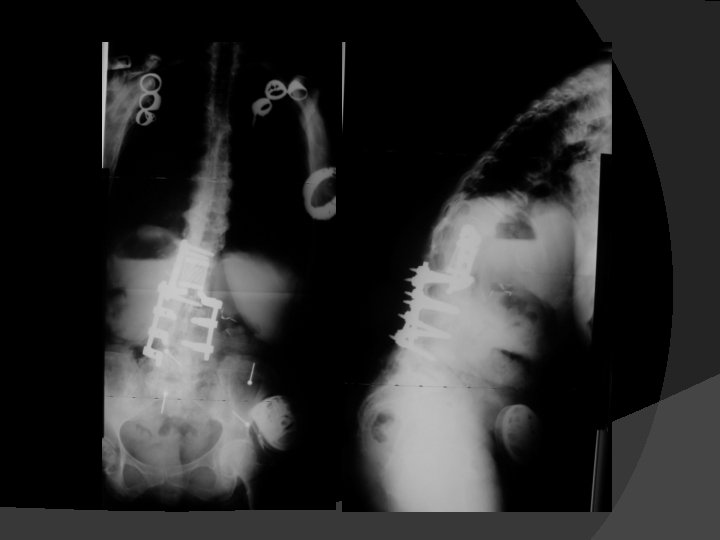

L 3 ASx PSO, T 10 – Pelvis PSF